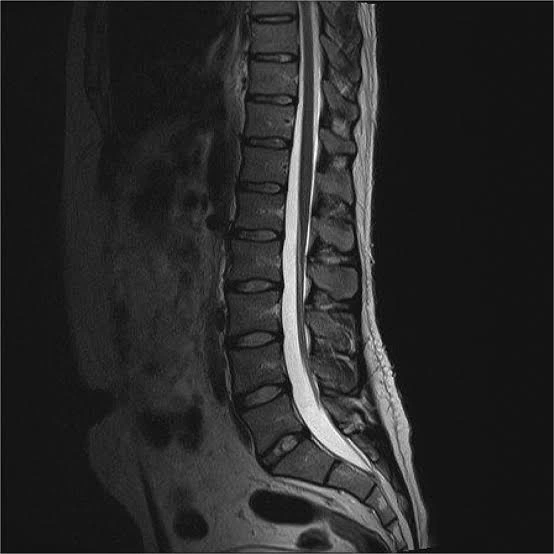

Seeing the words “lumbar disc herniation” on an MRI report is understandably stressful for many people. But in clinical practice, we often see something surprising: some individuals have clear lumbar disc herniation MRI findings and feel no pain at all, while others experience strong leg pain that feels like “sciatica” even when the MRI does not show a large herniation.

So the key question is this: Is pain truly caused by what we see on the MRI, or by the body’s clinical response? In this article, we explain the right way to interpret MRI results and how physiotherapy approaches lumbar disc herniation in a person-centered way.

Research has shown that disc bulges and even herniations can appear on MRI scans of people who have no back pain at all. That means lumbar disc herniation MRI findings alone are not enough to explain symptoms.

The size of a disc herniation on MRI does not always match how intense the pain feels.

- A larger herniation may cause few symptoms if it does not meaningfully affect the nerve

MRI is a valuable diagnostic tool, but it should not be the only factor guiding decisions.

With lumbar disc herniation, the real goal is not to “fix the report”—it’s to improve pain, function, and quality of life.